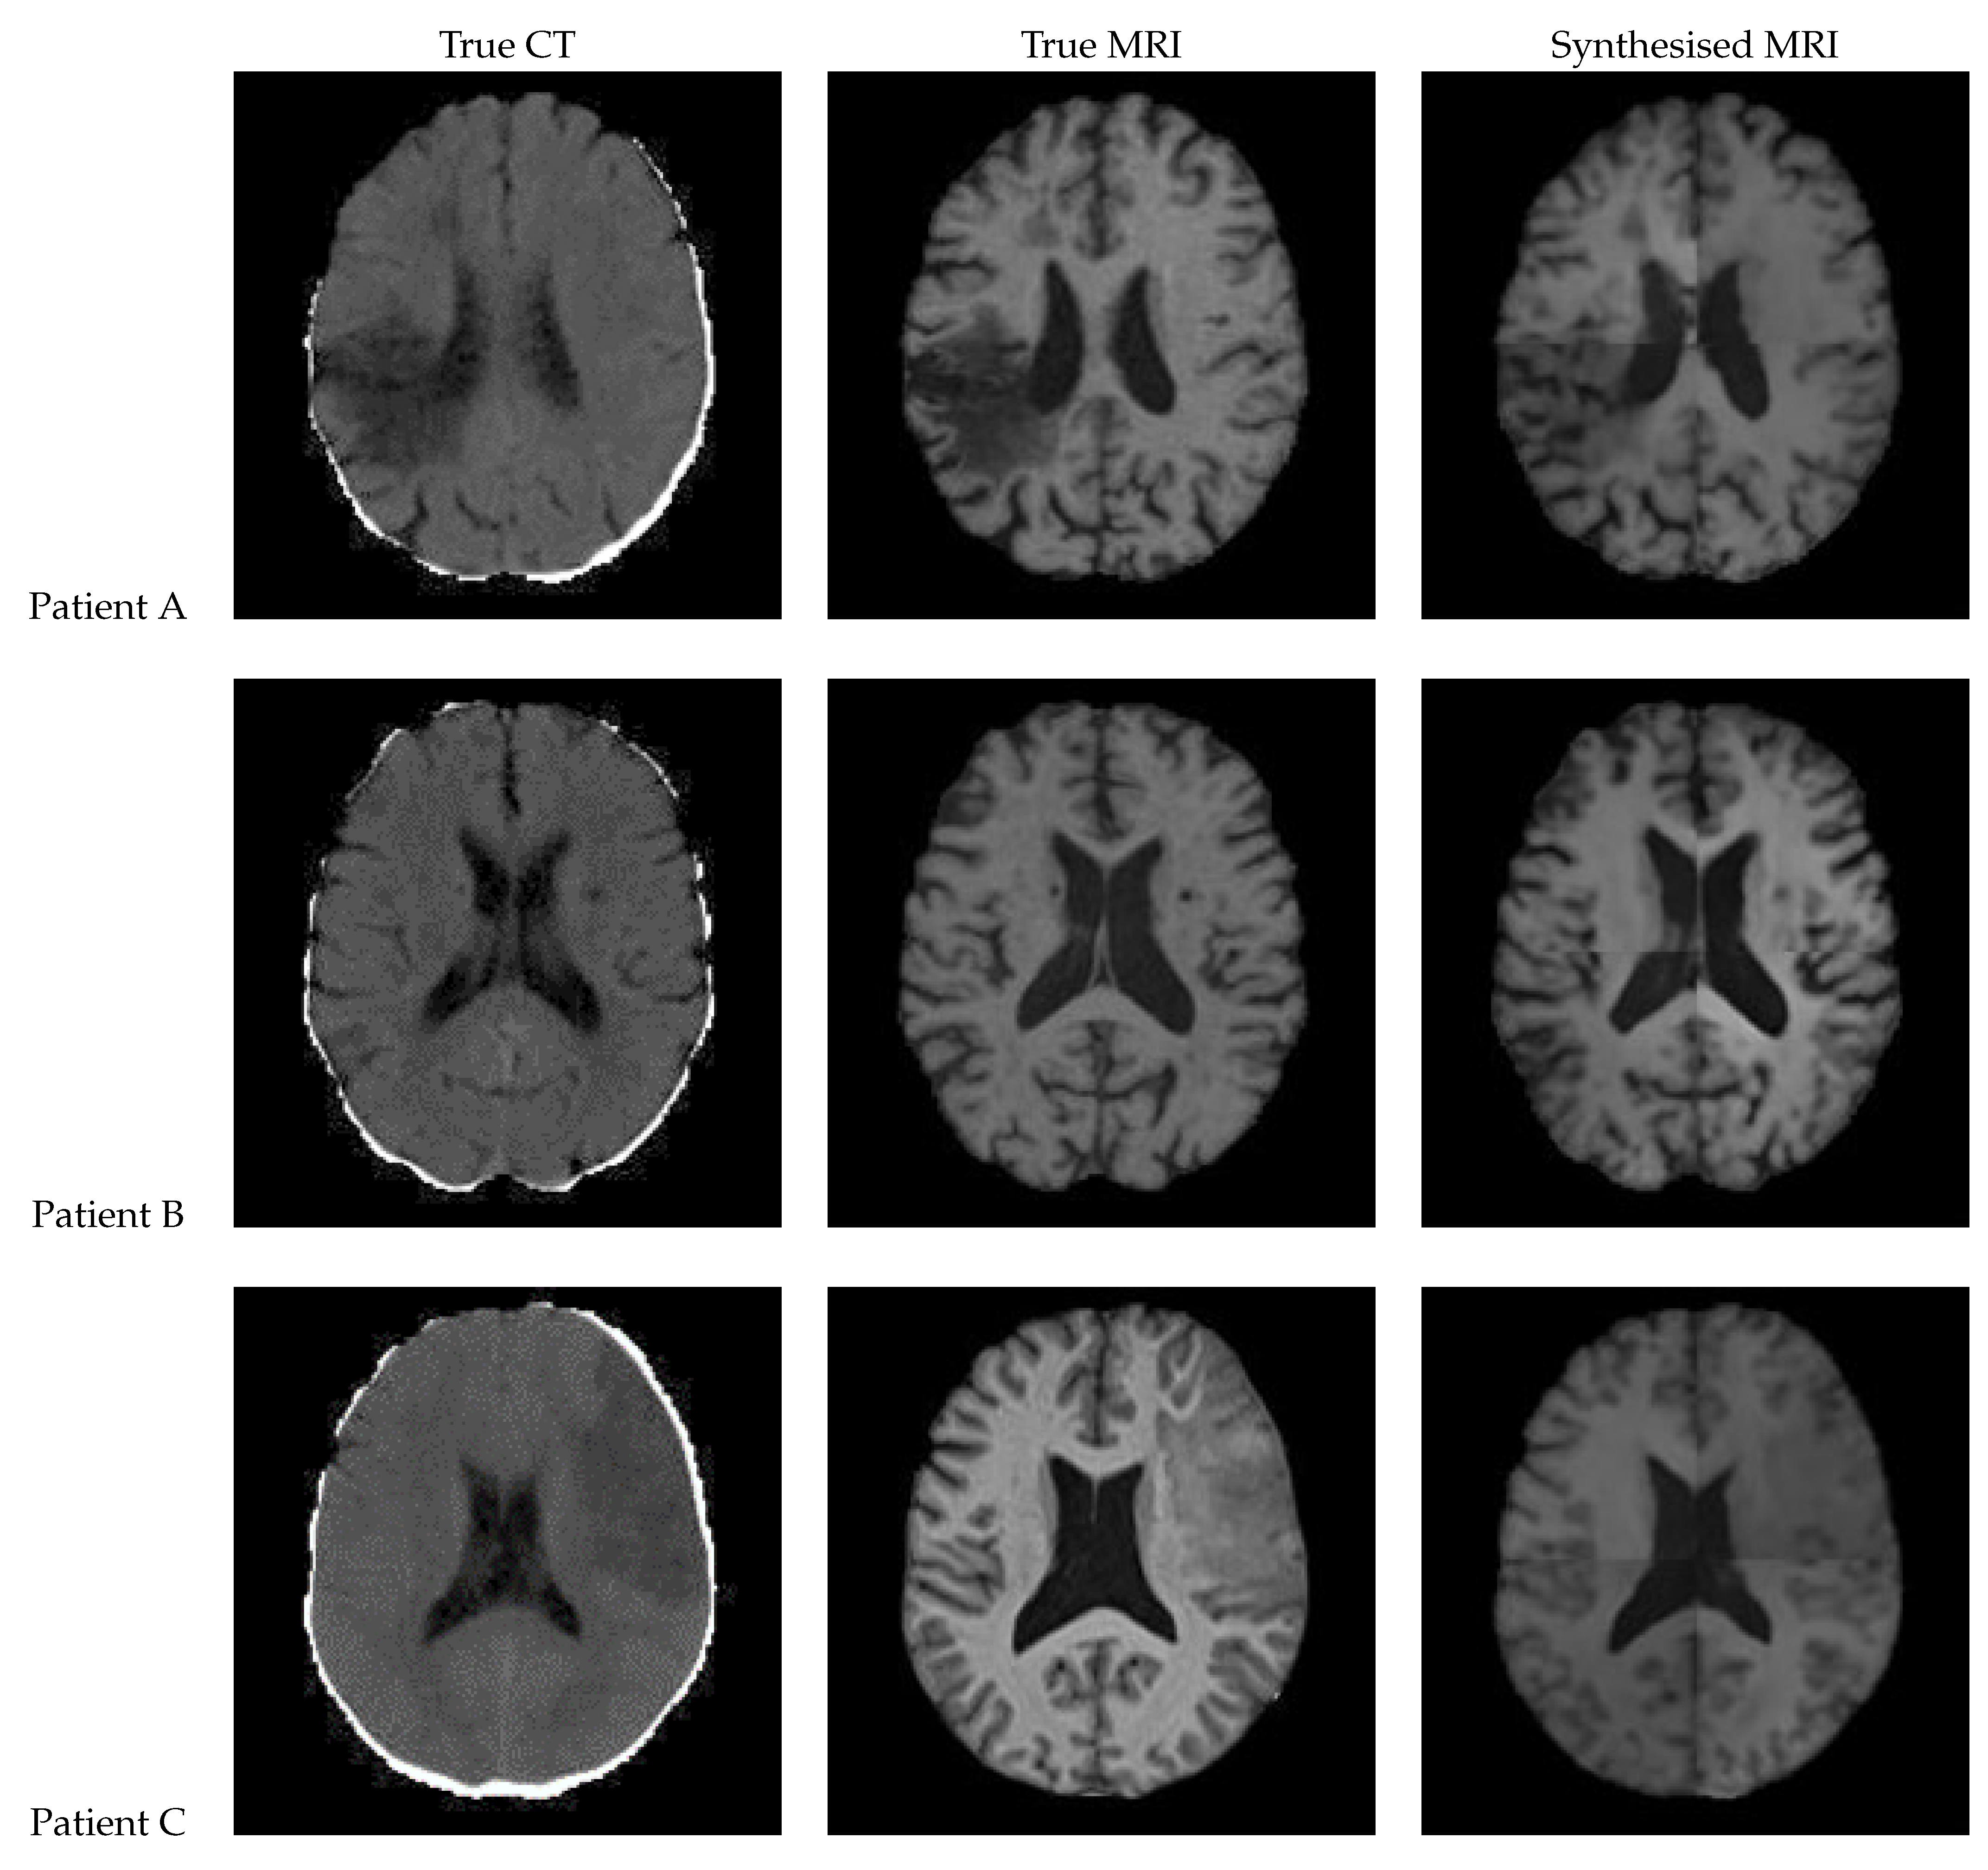

Figure 9. (a) MRI of Patient Alpha. (b) Target MRI for the registration task.

Registration of the CT, synthetic MRI, and true MRI was performed using the registration module in 3D Slicer to evaluate the usefulness of synthetic MRIs in reducing cross-modal registration to mono-modal registration. A randomly selected patient (Patient Alpha) from the training set, whose original MRI was not registered to the MNI152 atlas during the pre-processing, was chosen as the target registration space (Figure 9). Brain extraction using the SwissSkullStripper module of 3DSlicer was performed on Patient Alpha’s MRI to prepare it for registration. Patient H’s true CT, true MRI, and synthetic MRIs from each of the eight models were individually registered to Patient Alpha’s MRI using the BRAINS Registration in 3D Slicer, with the transformation matrices and registered volumes saved. All the transforms were applied to one volume to compare registration results without being affected by differences between synthetic and true MRIs. The CT underwent all nine saved transformations, and the CT transformation matrix from the true MRI was taken to be the optimal registration that all others were compared to. Matte’s Mutual Information (MMI) was calculated using the BRAINS metrics module in 3D Slicer to compare the nine other transformations.